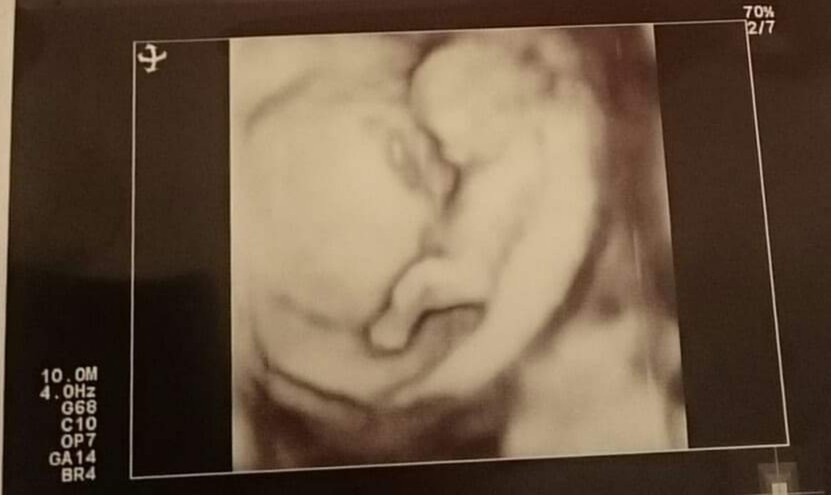

Doświadczone Mamusie jaka płeć dziecka według was jest na tych zdjęciach? Aktualnie 22tc

A czy u mnie coś podpowiecie?